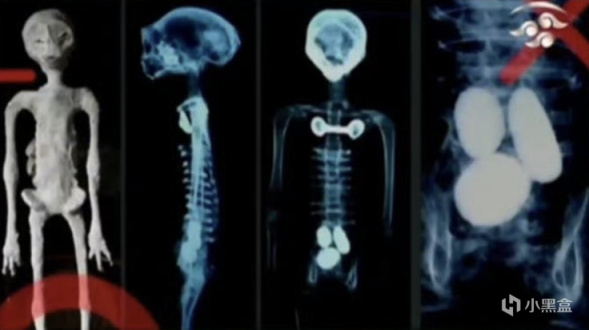

听证会上还展示了标本的 X 光片,专家们在宣誓后证明其中一具身体内有“卵”,而两具都有比如由非常稀有的金属锇之类制成的植入物...

奇异的手部被重点观察,其中一张手部 X 光片显示了“外星人”手掌的结构真相,“手指”是由打乱的人类掌骨、跖骨、趾骨用一种杂乱的方式拼接而成:

![]()

还有四肢也是拼凑的,“股骨”和“胫骨”是不同生长阶段的动物肱骨;